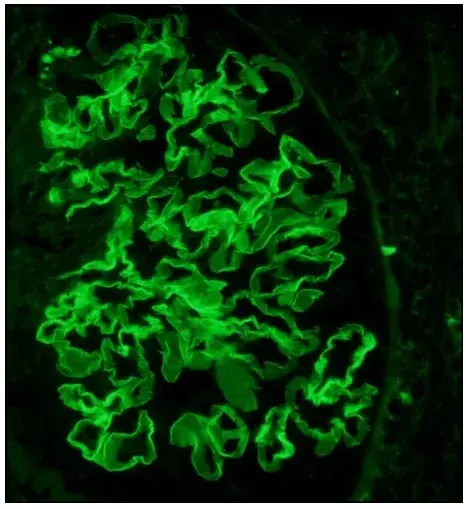

Proteinúria refratária em paciente com Nefrite Lúpica

Proteinúria refratária em paciente com Nefrite Lúpica